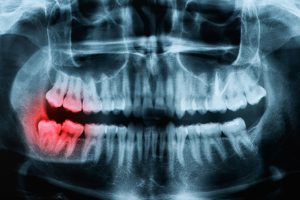

入念な診査・診断

通常のレントゲン写真と詳細な口腔内診査、そしてこれまでの経験に基づき、親知らずの埋まっている深さや、重要な神経・血管との位置関係を慎重に判断します。

これにより、抜歯の難易度や手術時間を予測し、不必要な侵襲を避けることが可能です。